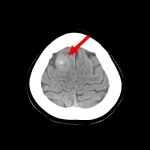

断層撮影